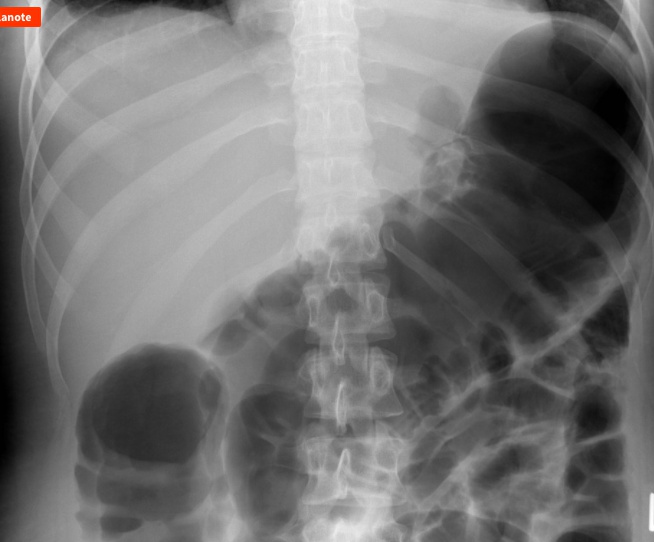

Imaging findings of gallstone ileus include:

Air in the hepatic bile ducts

Small bowel obstruction with an air-fluid level

Gallstones in the ileocecal valve

CT scan is the preferred test for gallstone ileus. It can show all of the features of gallstone ileus, including the fistula between the gallbladder and intestine. Abdominal X-ray may reveal air in the biliary tract and an air-fluid level in the ileus.